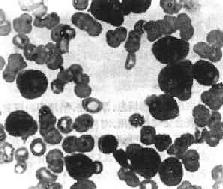

1.周围血像早期即出现贫血,白细胞总数多少不等,白细胞增多性与不增多性者约各占一半。白细胞增多性者,白细胞总数多在2万~5万/μl,常呈进行性上升,可高达10至数10万。其中有大量原始和幼稚细胞(图11-6)。白细胞不增多性白血病的白细胞计数可正常或减少,有时可降低至1000~3000/μ1,较难找到原始或幼稚细胞。血小板减少有时达1万/μ1以下。

图11-6 急性粒细胞性白血病

周围血内有大量原始粒细胞